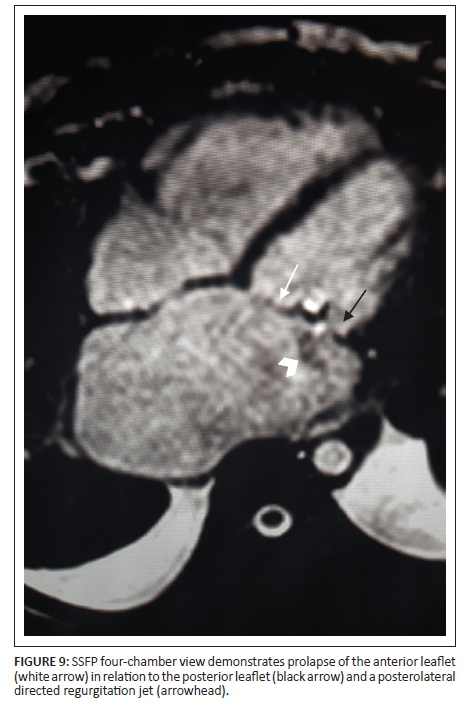

With leaflet prolapse, as with tears and clefts, the flow jet is eccentric. In mitral valve prolapse, the jet is directed antero-medially towards the septum with prolapse of the posterior leaflet, and is postero-central or postero-lateral with anterior leaflet prolapse. In the instance of bi-leaflet prolapse, the flow jet is in a postero-medial direction (Figure 9).8